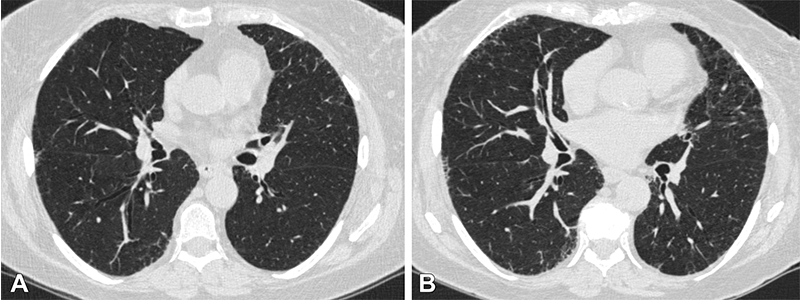

Axial chest CT scans at (A) visit 1 and (B) visit 2 at the level of the takeoff of the right middle bronchus of a participant with 1.2 annual percentage quantitative interstitial abnormality progression. The female participant was 62 years old at visit 1 and 67 years old at visit 2 and a current smoker at both visits, with a 47.5 pack-year history at visit 2. This participant had four subsequent acute respiratory disease (ARD) events and three subsequent severe ARD events.